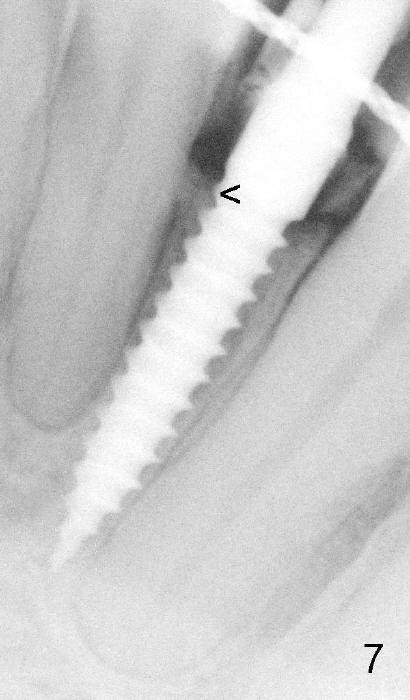

Fig.7 is taken 10 months postop. The provisional has not been replaced by a definitive restoration. The 1st thread is equicrestal (<).